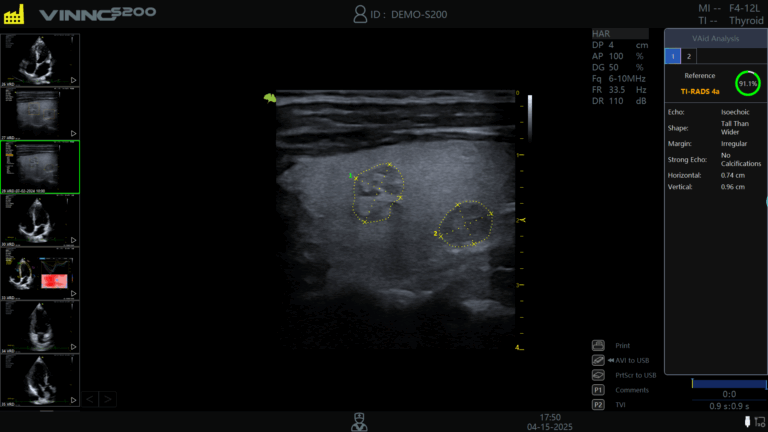

- VSpeckle – foloseste algoritmi de procesare adaptiva pentru a elimina zgomotul din imagini, fara sa se piarda informatia esentială. Acest lucru este un avantaj util în examinarea organelor cu textura complexa (ficat, tiroida, pancreas), unde diferentele subtile conteaza.

- VFusion – Aceasta functie face ceea ce numim „image compounding”: combina mai multe imagini captate din unghiuri diferite intr-o singura imagine finala, constituind un avantaj in diferentierea leziunilor de tesutul sănătos. Este folosita in radiologie, imagistica abdominala si musculoscheletala, unde claritatea si detaliile fac diferenta.

Ecograf VINNO S300: performanta si inovatie in practica medicala

Ecograful VINNO S300 este un model mai recent, creat pentru a raspunde cerintelor medicilor care doresc atat calitate superioara a imaginii, cat si functionalitati inteligente.

- Imagini clare 2D si evaluare precisa a fluxului sanguin

- Modul Ultrasense pentru optimizare automata

- Ideal pentru aplicatii musculo-scheletice, gastroenterologie si obstetrica